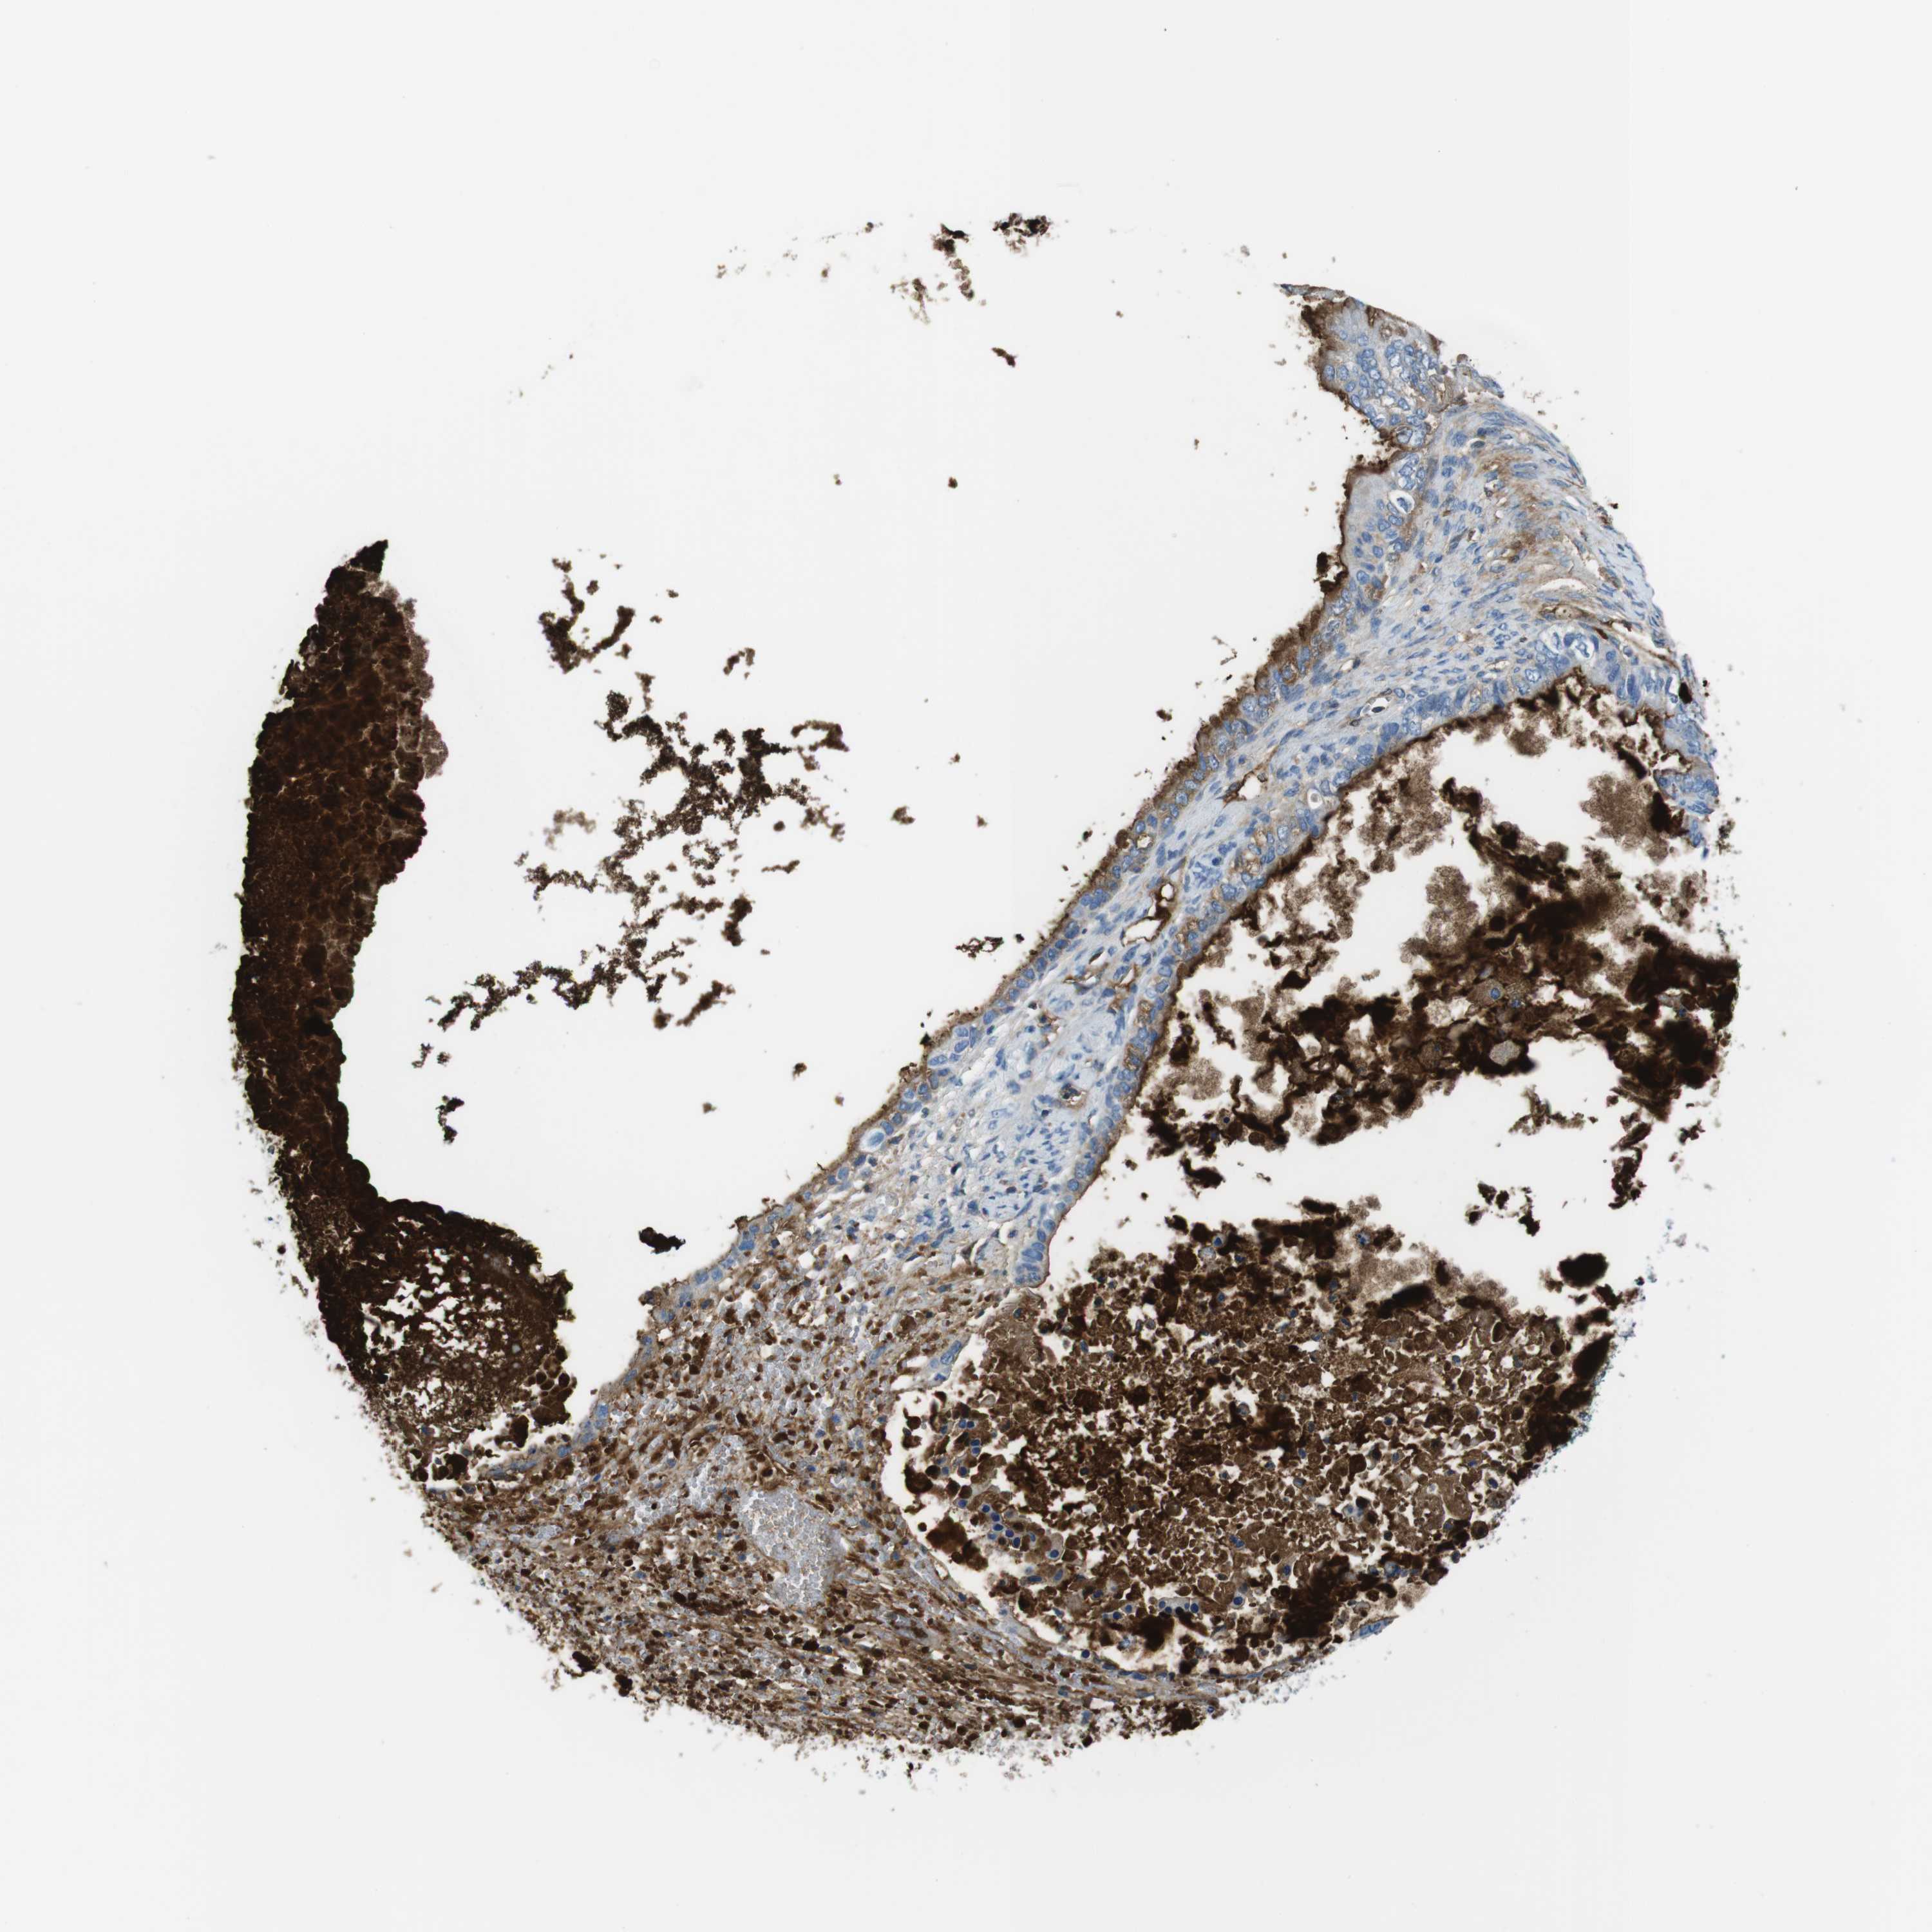

OVARIAN CANCER - Protein expressioni

A mouse-over function shows sample information and annotation data. Click on an image to view it in a full screen mode. Samples can be filtered based on level of antibody staining by selecting one or several of the following categories: high, medium, low and not detected. The assay and annotation is described here.

Note that samples used for immunohistochemistry by the Human Protein Atlas do not correspond to samples in the TCGA dataset.

Antibody stainingi

Antibody staining in the annotated cell types in the current human tissue is reported as not detected, low, medium, or high, based on conventional immunohistochemistry profiling in selected tissues. This score is based on the combination of the staining intensity and fraction of stained cells.

Each image is clickable and will lead to virtual microscopy that enables deeper exploration of all samples and also displays staining intensity scores, fraction scores and subcellular localization as well as patient and tissue information for each sample.

Antibody CAB015377

Cystadenocarcinoma, serous, NOS

Carcinoma, endometroid

Cystadenocarcinoma, mucinous, NOS

Carcinoma, NOS